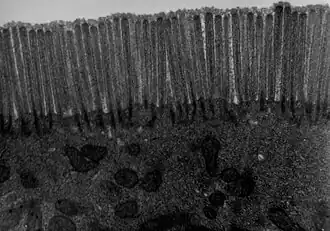

The interior surface of the jejunum—which is exposed to ingested food—is covered in finger–like projections of mucosa, called villi, which increase the surface area of tissue available to absorb nutrients from ingested foodstuffs. The epithelial cells which line these villi have microvilli. The transport of nutrients across epithelial cells through the jejunum and ileum includes the passive transport of sugar fructose and the active transport of amino acids, small peptides, vitamins, and most glucose. The villi in the jejunum are much longer than in the duodenum or ileum.

The jejunum contains very few Brunner's glands (found in the duodenum) or Peyer's patches (found in the ileum). However, there are a few jejunal lymph nodes suspended in its mesentery. The jejunum has many large circular folds in its submucosa called plicae circulares that increase the surface area for nutrient absorption. The plicae circulares are best developed in the jejunum.

- The villi of the jejunum look like long, finger-like projections, and are a histologically identifiable structure.

Transmission electron microscope (TEM) image of human jejunum

Transmission electron microscope (TEM) image of human jejunum -